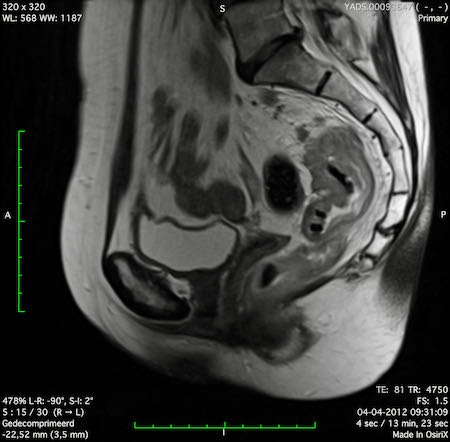

Hình ảnh

Các hình ảnh được cung cấp cho thấy ung thư biểu mô tế bào nhẫn với tình trạng dày lan tỏa thành trực tràng, hình ảnh bia bắn điển hình, và sự xâm lấn mỡ mạc treo trực tràng.